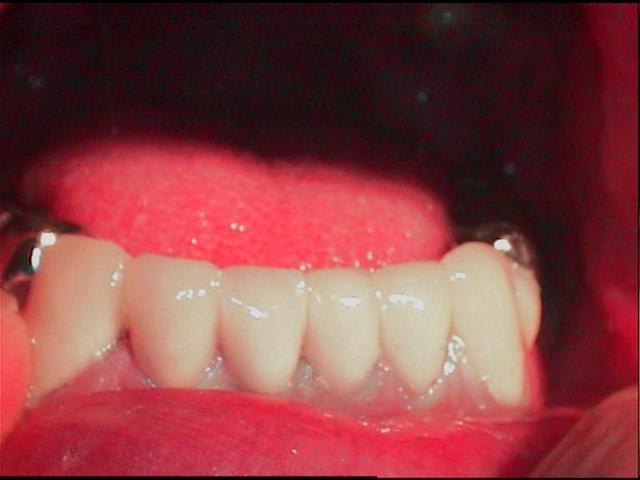

Les 4 incisives mandibulaires, sont nécrosées.

voila Jay, un cas qui ressemble au tien. bon courage.

j'ai eu un peu le meme genre de cas adressé, mais plus simple que le tien. j'étais un peu bridé pour le traitement a cause d'un bridge quasi complet en haut

je crois que le cas de Jay est plus complexe, et compliqué aussi par des mylolyses (visibles faces vest des incisives) et dont l'évolution, meme apres correction de l'occl, pourrait nuire a la retention ( sur les dents qu'il garderait vivantes)